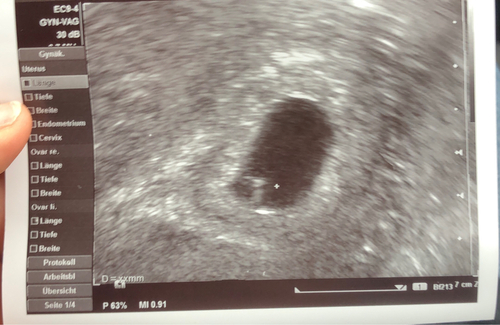

Ich hatte heute meinen ersten Termin, um die Schwangerschaft ärztlich offiziell feststellen zu lassen. Da das Herzlein geflimmert hat, durften wir sogar ein Foto mitbekommen. Da ist es unser zweites kleines Wunder. 🥹 Ich kann es kaum fassen und muss immer wieder weinen. ❤️